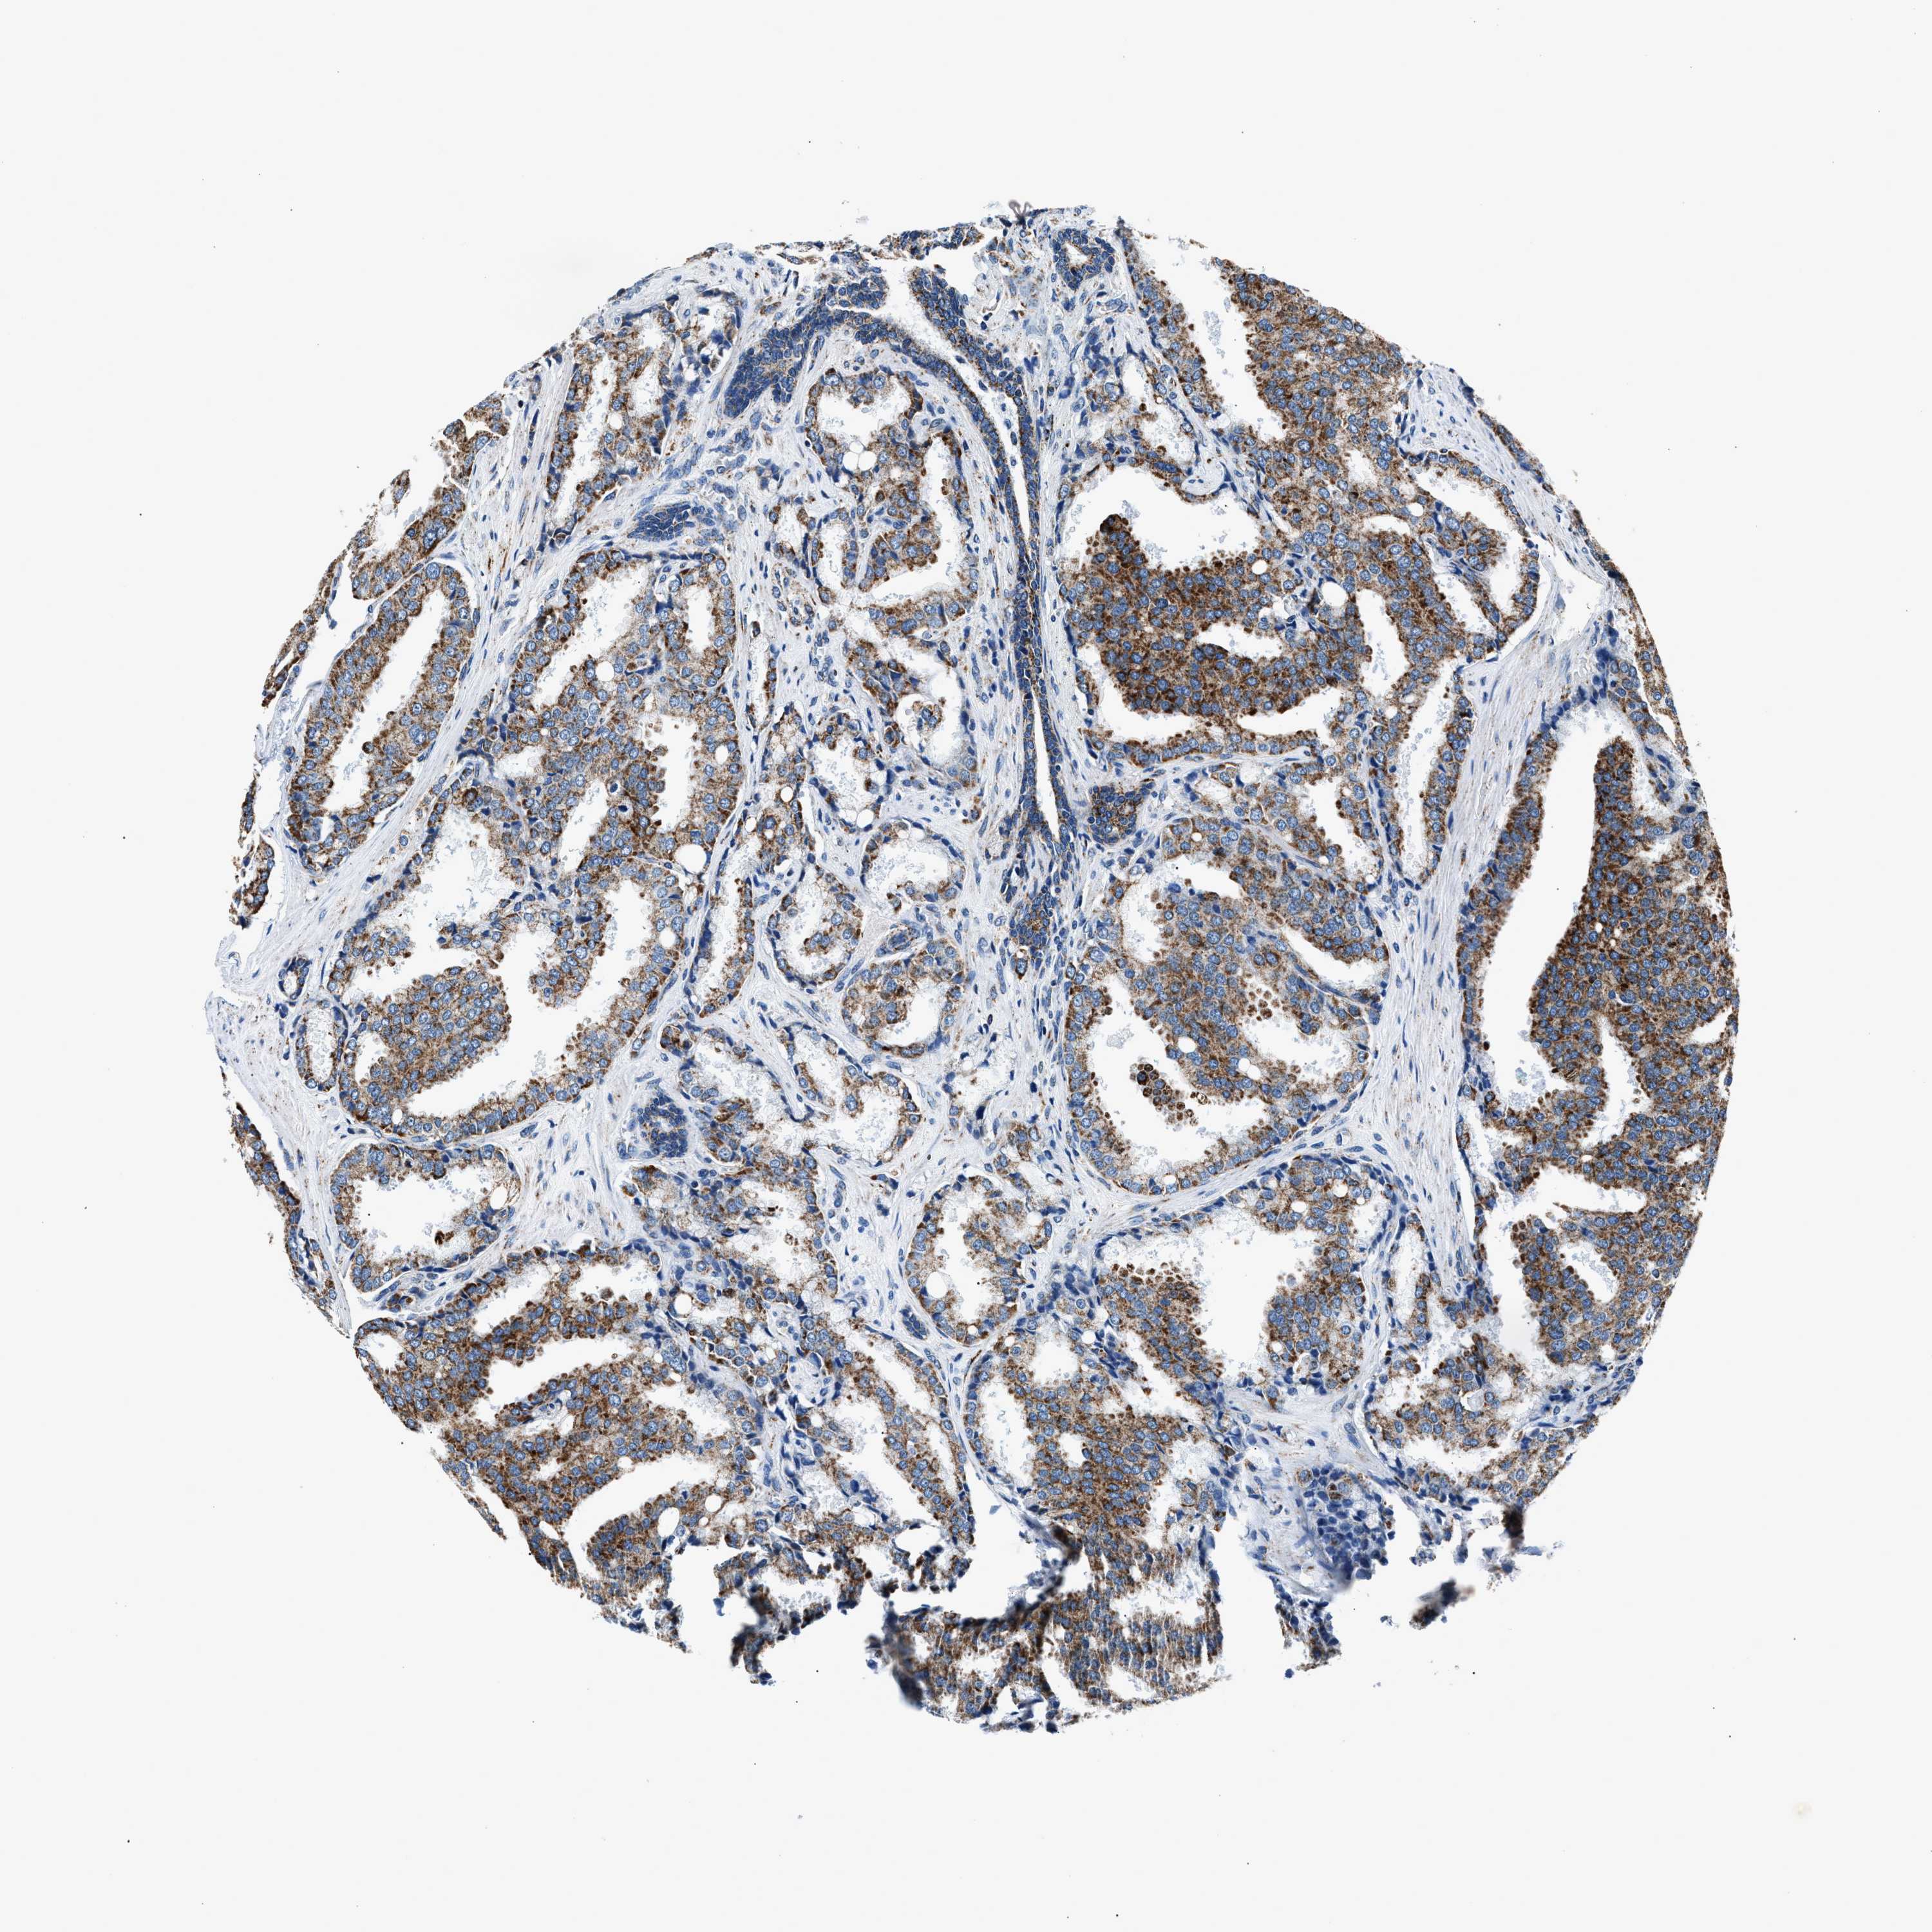

PROSTATE CANCER - Protein expressioni

A mouse-over function shows sample information and annotation data. Click on an image to view it in a full screen mode. Samples can be filtered based on level of antibody staining by selecting one or several of the following categories: high, medium, low and not detected. The assay and annotation is described here.

Note that samples used for immunohistochemistry by the Human Protein Atlas do not correspond to samples in the TCGA dataset.

Antibody stainingi

Antibody staining in the annotated cell types in the current human tissue is reported as not detected, low, medium, or high, based on conventional immunohistochemistry profiling in selected tissues. This score is based on the combination of the staining intensity and fraction of stained cells.

Each image is clickable and will lead to virtual microscopy that enables deeper exploration of all samples and also displays staining intensity scores, fraction scores and subcellular localization as well as patient and tissue information for each sample.

Antibody HPA019522

Antibody HPA021002

Staining

High

Medium

Low

Not detected

Intensity

Strong

Moderate

Weak

Negative

Quantity

>75%

75%-25%

<25%

None

Location

Nuclear

Cytoplasmic/membranous

Cytoplasmic/membranous,nuclear

Adenocarcinoma, High grade

Adenocarcinoma, Low grade